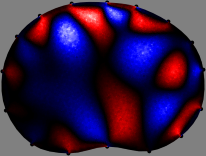

To explain the FER method, we closely examine the correlations among column vectors of the sensitivity matrix , described in Fig. 2. The correlation between and can be expressed as

for [23]. This shows that the column vector is like an EEG (electroencephalography) data induced by dipole sources with directions at locations . Given that two dipole sources at distant locations produce mutually independent data, the correlation between and decreases with the distance between and . Fig. 2 shows a few images of the correlation as a function of for four different positions . The correlation decreases rapidly as the distance increases. In the green regions where the correlation is almost zero, is nearly orthogonal to .

Fig. 2 shows that if and are far from each other, the corresponding columns of the sensitivity matrix are nearly orthogonal. This somewhat orthogonal structure of the sensitivity matrix motivates an algebraic formula that directly computes the local ensemble average of conductivity changes at each point using the inner product between changes in the data and a scaled sensitivity vector at that point: